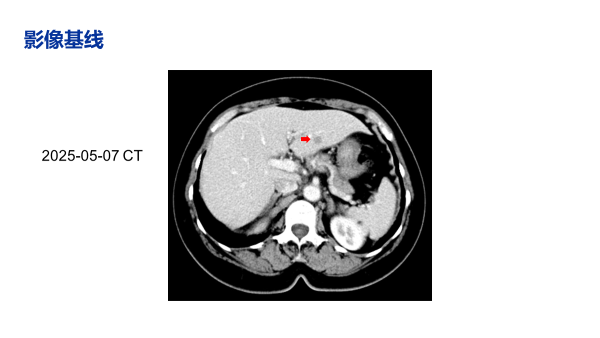

治疗近2个月后(2025-08-04),影像学评估疗效为部分缓解(PR),肝脏转移灶较基线明显缩小。